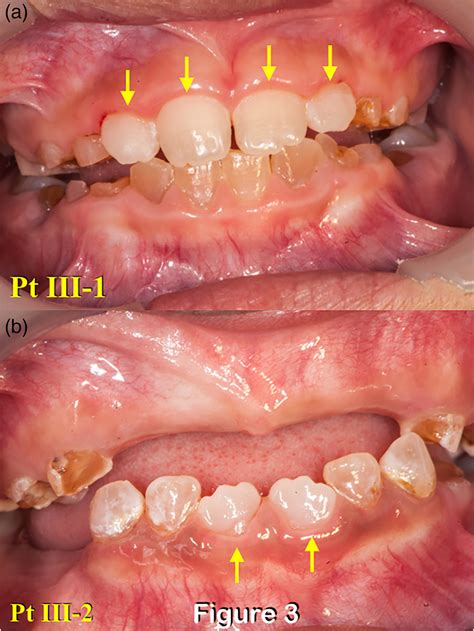

• Discoloration: Teeth often appear translucent, opalescent, or exhibit a blue-gray to yellow-brown hue.

• Structural Fragility: Because the dentin is soft and disorganized, the enamel often chips away easily, exposing the underlying dentin to rapid attrition.

• Radiographic Features: X-rays typically reveal bulbous crowns, a constricted cervical area, and abnormally thin roots. In some cases, pulp chambers may appear small or completely obliterated by secondary dentin formation.